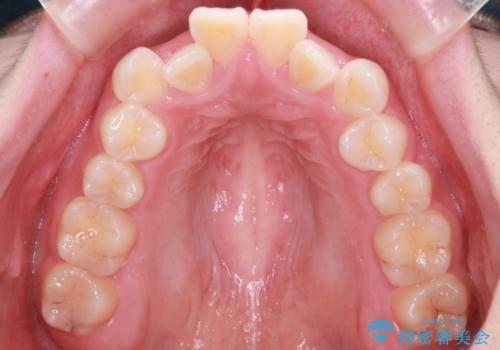

【抜歯インビザ】前歯の凸凹をなおしたい

- 前歯の凸凹を主訴に来院されました。

前歯はあまり下げる必要がなかったため、上下左右の第二小臼歯抜歯を行う治療計画としました。

途中、臼歯の近心傾斜を認めましたが、追加アライナーを使用することでリカバリーを行いながらインビザラインのみで治療を完了することができました。